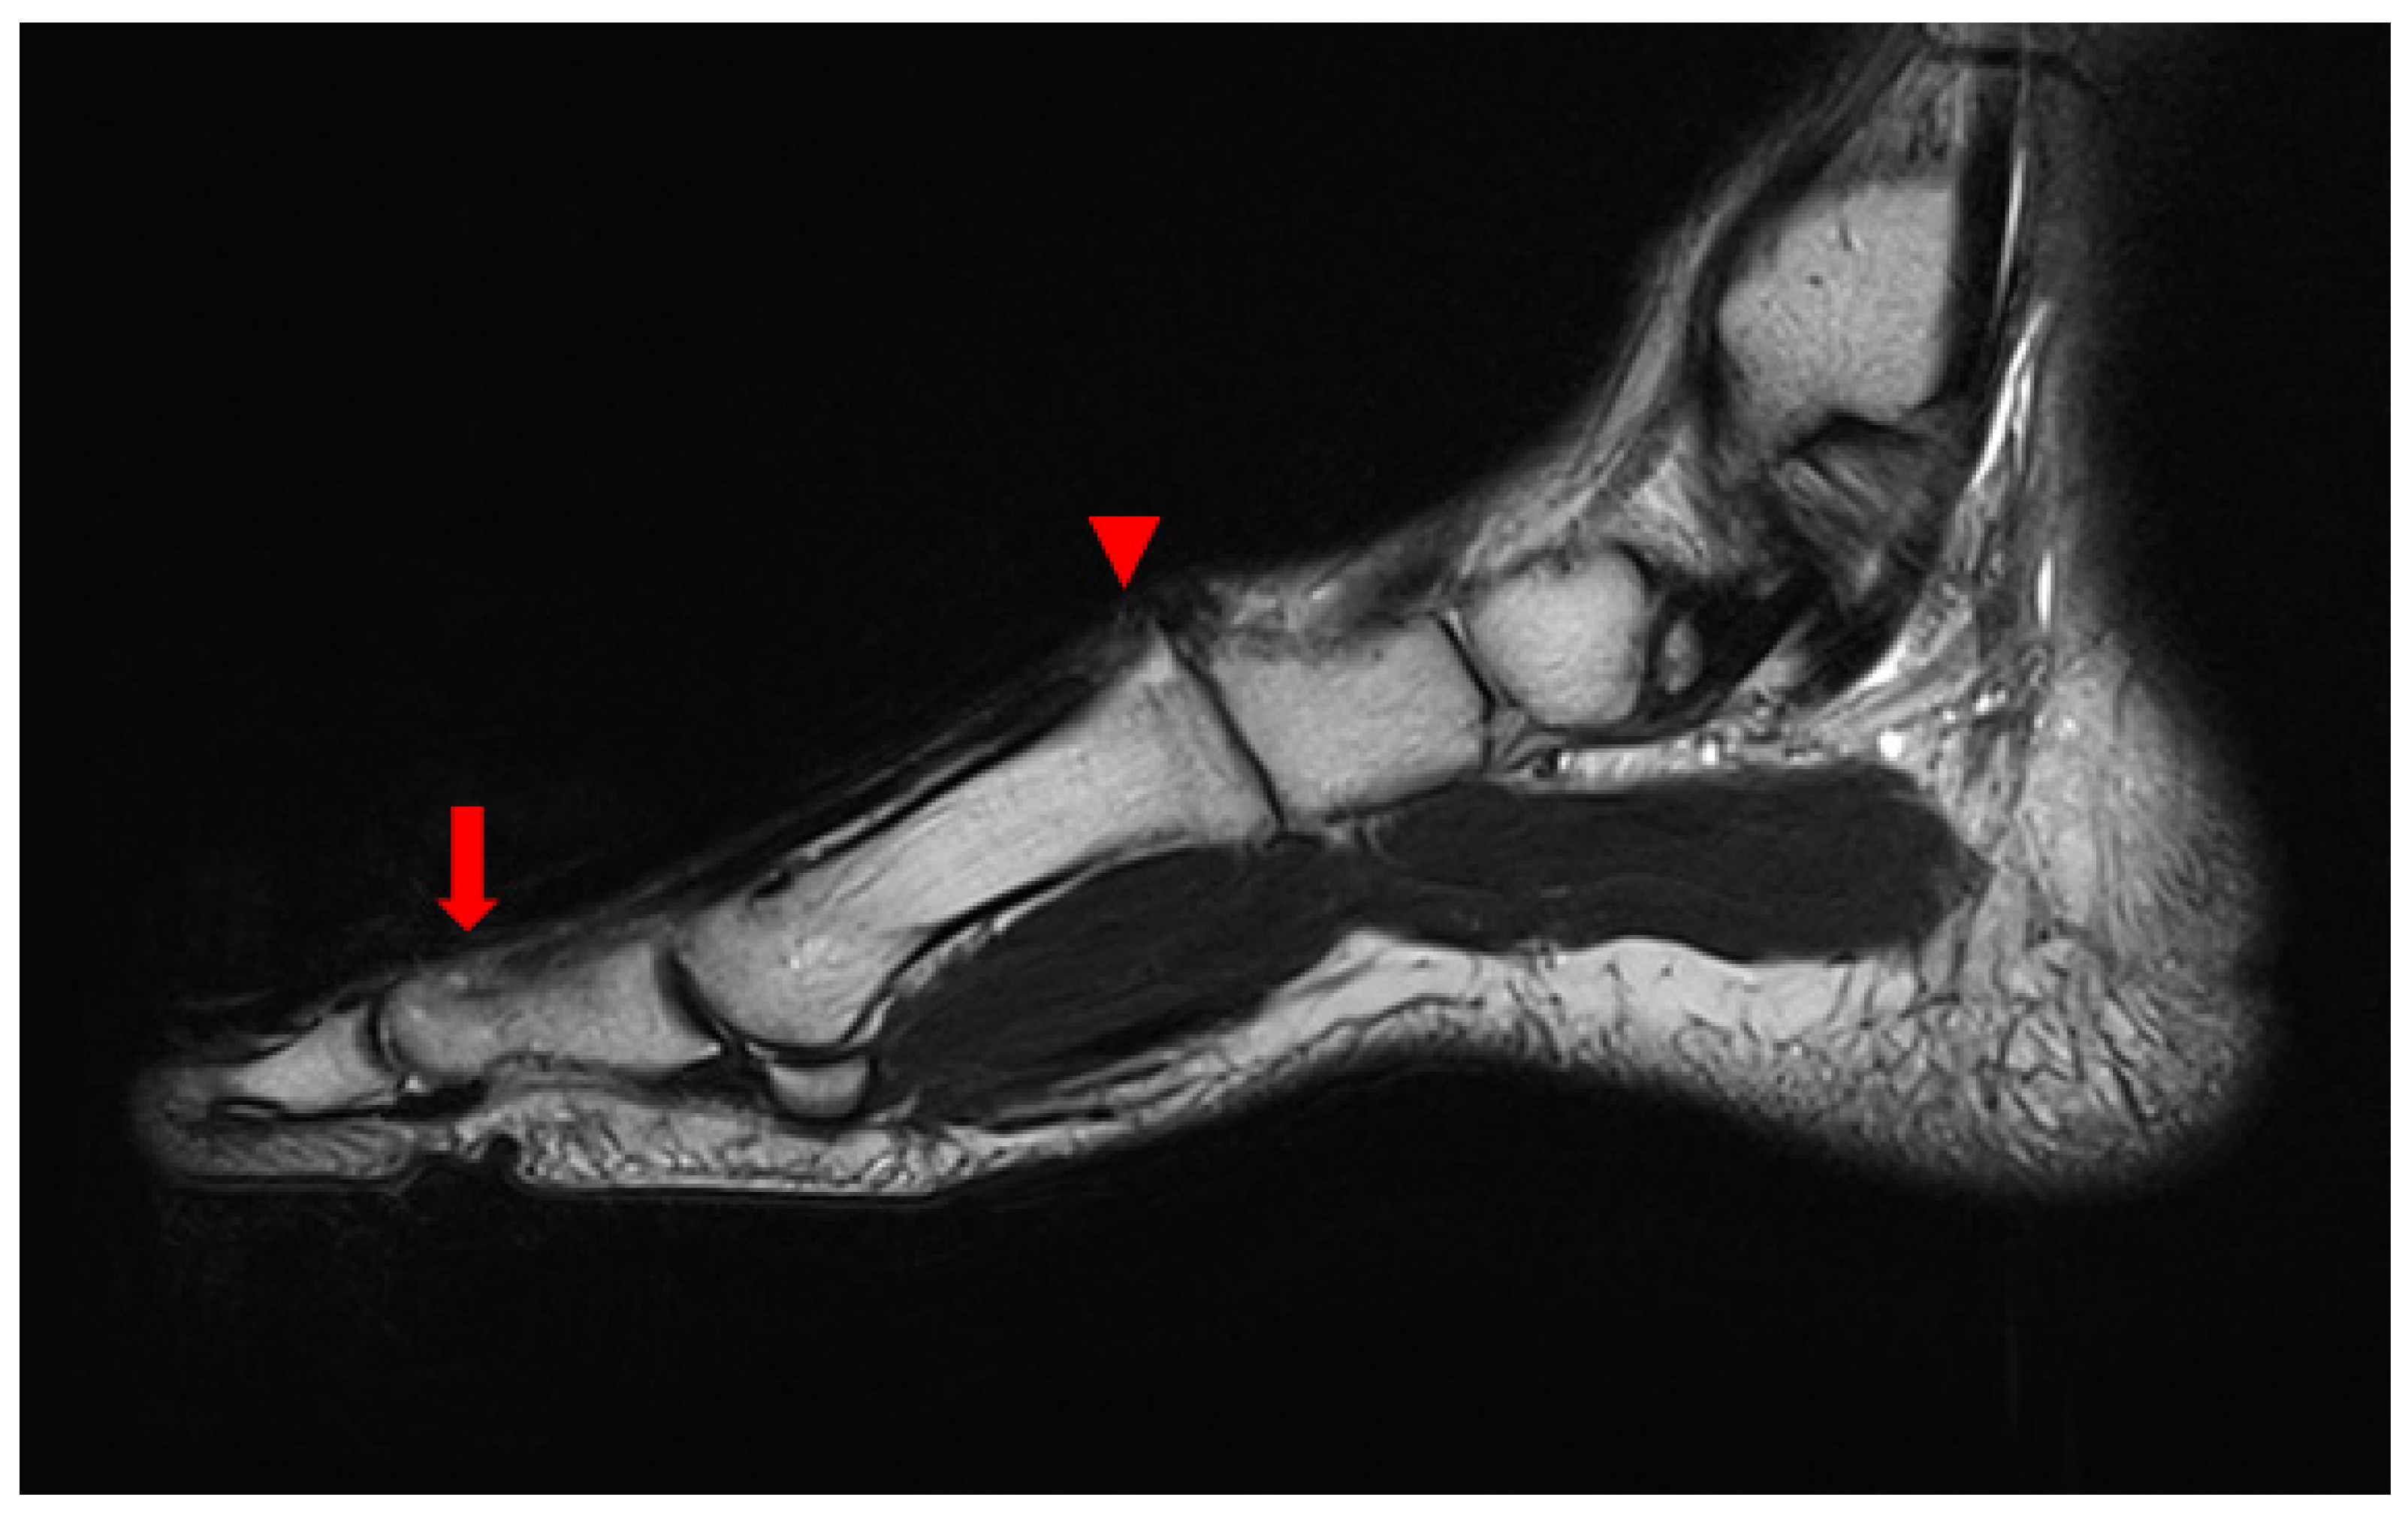

2. Case Presentation

2.1. Preoperative Evaluation